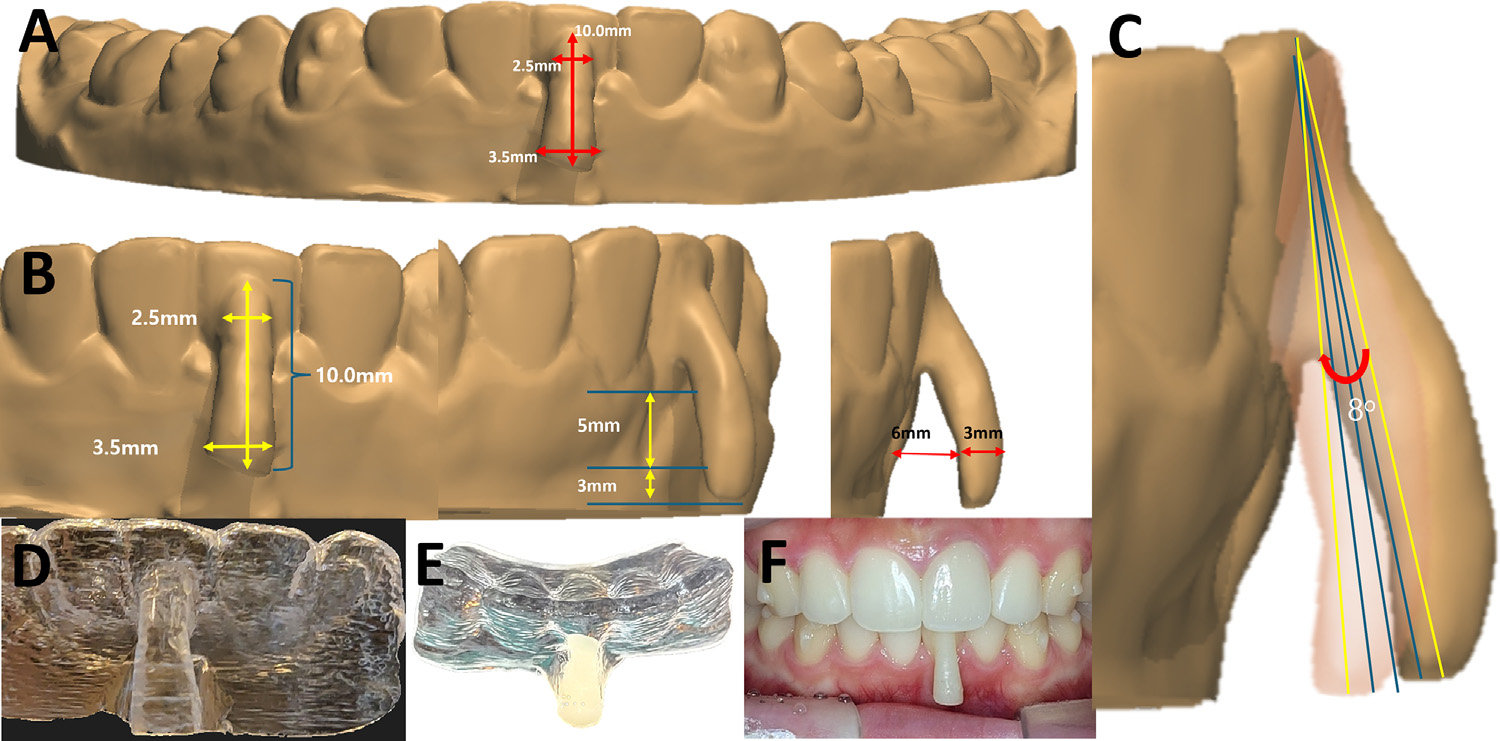

투명교정 전문기업 시스루테크㈜의 홍경재 대표가 개발한 시스루 얼라이너 ‘오버행잉 어태치먼트(Overhanging Attachment)’ 기술이 세계 교정학계의 주목을 받고 있다.

홍 대표는 해당 기술을 활용해 수술 없이 잇몸퇴축(gingival recession)을 회복시키는 데 성공했으며, 이 연구 결과는 미국 교정학회 공식 학술지 ‘American Journal of Orthodontics and Dentofacial Orthopedics Clinical Companion (AJO-DO Clinical Companion)’ 2025년 10월호에 게재됐다.

이번 논문은 국내 최초로 투명교정만으로 퇴축된 잇몸을 재생시킨 임상 보고로, 하악 전치부에서 5mm의 잇몸퇴축이 11개월간의 교정치료 후 1mm로 회복되는 임상 결과를 확인했다. 치조골과 잇몸조직이 자연스럽게 복원되는 과정을 객관적 데이터로 제시했다는 점에서 의미가 크다.

‘오버행잉 어태치먼트’는 치근 이동 시 발생하는 토크(torque)를 정밀 제어해, 치아의 중심저항점(center of resistance)에 가까운 위치에서 힘을 전달하도록 설계됐다. 이를 통해 정확한 치체이동(root movement)이 가능해지고, 결과적으로 잇몸재생이 유도된다.